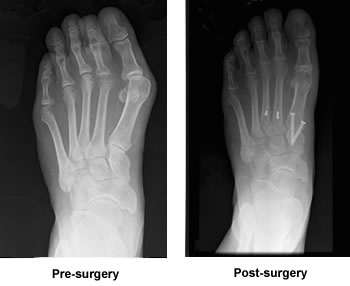

Marathoner Resumes Running after his Bunion/Hammertoe Surgery

My condition was quite painful. Three toes on my left foot were dislocated. The large toe had dislocated due to the bunion pulling the adjacent bones apart. The second and third toes had dislocated in what would be classified as 'hammer' toes where the metatarsal bones then slid under the toes themselves making even normal walking painful. The surgery itself was a blur and over in a matter of hours. I was home in bed that afternoon.